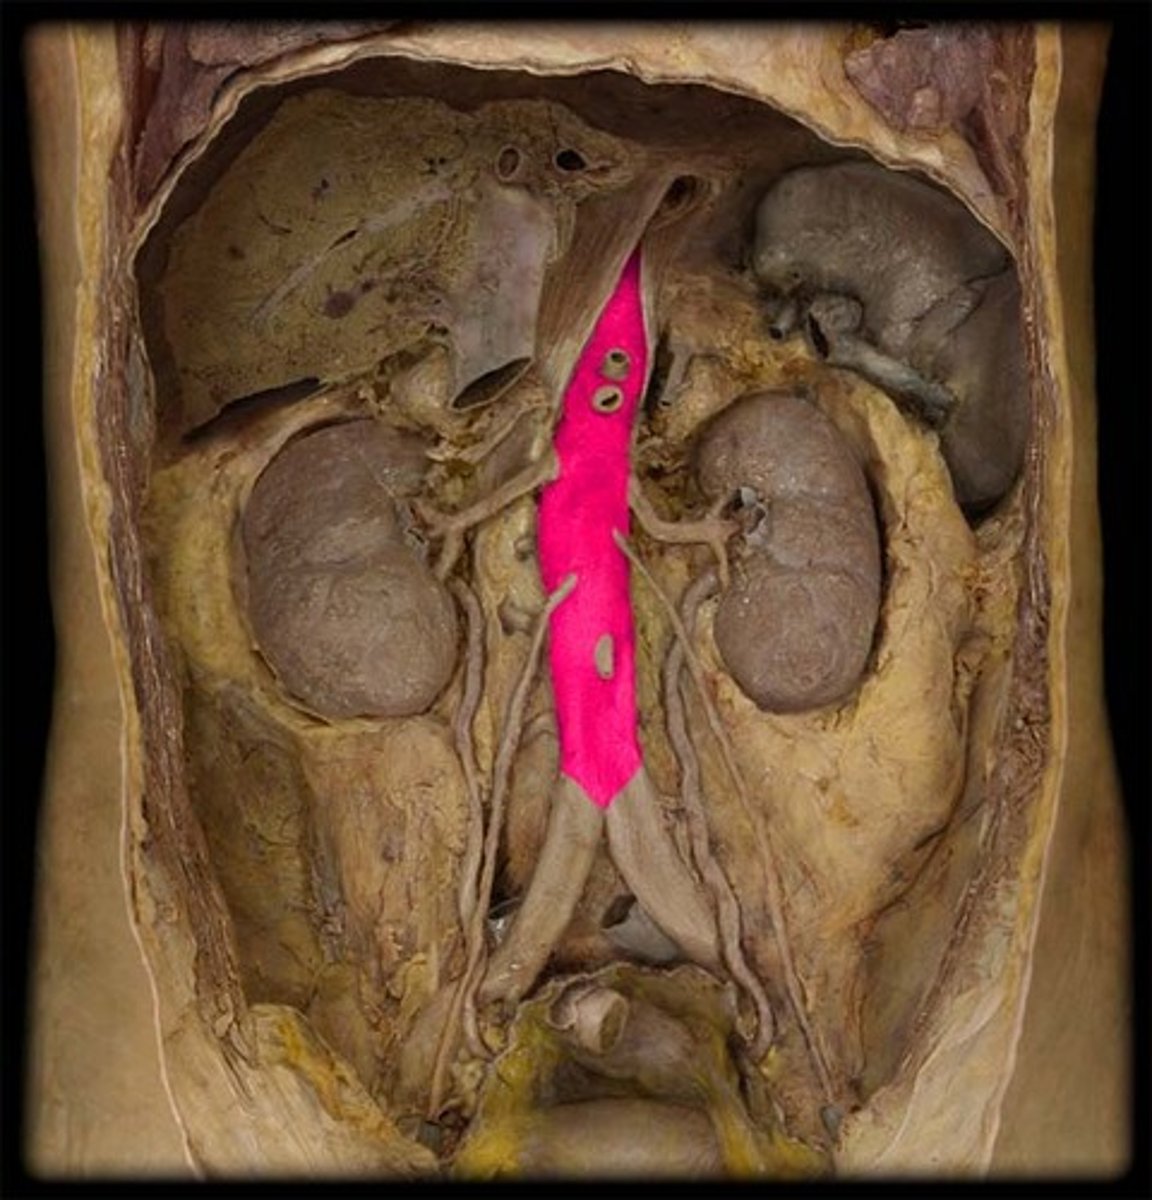

abdominal aorta

continuation of the thoracic aorta that runs through the abdominal cavity

renal arteries

The two small branches of the abdominal aorta that supply the kidneys

celiac trunk

Large unpaired branch of the abdominal aorta that supplies the liver, stomach, and spleen. 1st

superior mesenteric artery

unpaired. to middle digestive tube. below celiac trunk. 2nd

inferior mesenteric artery

unpaired. to lower digestive tube. cord like, 3rd